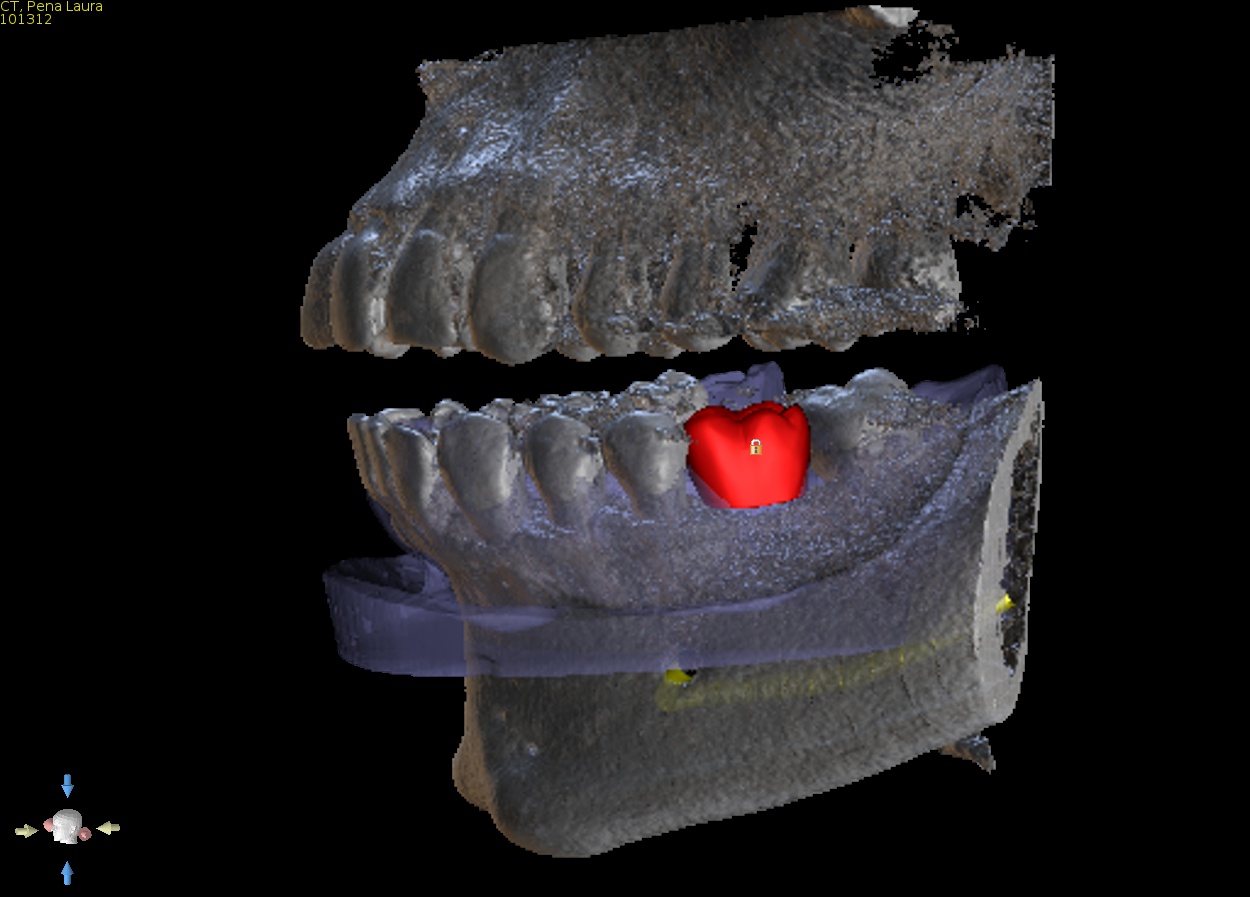

1. CBCT and model merge

Supply a CBCT of the patient and a PVS impression or intra oral scan. We will accurately merge the model with the CBCT so the guide can be made to fit accurately and be tooth and if need be tissue supported. This is a special feature that allows us to offer perfectly fitting guides. Edentulous solutions are also available including tissue or bone supported guides.

2. Virtual implant placement

Supply us with the implant brand and size and we will position it exactly to your specifications and in relation to the virtual final tooth position. We will send a written report for you to check and note any changes if needed. We will not make the guide until you are 100% satisfied with the virtual placement. Alternatively use free software to plan the case yourself and send us the plan file and we can make the guide from that.